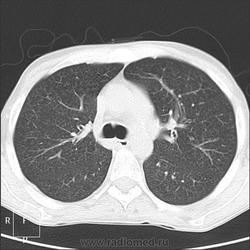

Прозрачность обеих легких равномерно неинтенсивно снижена за счет наличия множественных, плохо дифференцируемых мелкоочаговых теней, сливающихся между собой и расположенных главным образом во внутренних отделах легких, ближе к корням легких, образуя картину «бабочки». Сосудистый рисунок диффузно усилен, в виде радиальных извитых теней за счет перибронхиальной и периваскулярной инфильтрации. Линейные тени пластинчатых ателектазов. Корни легких малоструктурны. Органы средостения не смещены. Сердечная тень не увеличена."

Я не вижу "Бабочку", а Вы?

Из-за почечной недостаточности контрастирования не будет. Такая картина в легких мне впервые попадается. Есть несколько вариантов, но очень хочется услышать мнения коллег! Какие будут мысли?

В легких - рентгенограмму я описала как усиление за счет интерстициального компонента. Корень кажется обрубленным: из-за асцита высоко стоит диафрагма, нижние отделы легких поджаты. Пневмосклероза я не вижу. А по КТ не знаю, как интерпретировать: интерстициальный отек, токсический васкулит?

Тогда, учитывая всё вышесказанное, вероятно интерстициальный отёк ( гипопротеинемия, почечная недостаточность, токсическое поражение...)

Интерстициальный отек легких. Хронический калькулезный панкреатит. Киста хвоста поджелудочной железы, без биопсии уверенно раковое перерождение не исключить. Киста сальниковой сумки /вероятно тоже панкреатического генеза/. Жировой гепатоз печени с портальным циррозом /биопсия/. Камень устья? пузырного протока. Геморрагические кисты почек??? Асцит.

Парочка моих шаблонов, наверное первый соответствует настоящему состояниюПрозрачность обеих легких равномерно неинтенсивно снижена за счет наличия множественных, плохо дифференцируемых мелкоочаговых теней, сливающихся между собой и расположенных главным образом во внутренних отделах легких, ближе к корням легких, образуя картину «бабочки». Сосудистый рисунок диффузно усилен, в виде радиальных извитых теней за счет перибронхиальной и периваскулярной инфильтрации. Линейные тени пластинчатых ателектазов. Корни легких малоструктурны. Органы средостения не смещены. Сердечная тень не увеличена.

Прозрачность обеих легких неравномерно, преимущественно в нижних отделах, неинтенсивно снижена за счет наличия множественных, плохо дифференцируемых крупноочаговых теней, сливающихся между собой и расположенных главным образом во внутренних отделах легких, ближе к корням легких, образуя картину «бабочки». В прикорневых и паравертебральных отделах значительное усиление сосудистого рисунка, размытого грубопетлистого, обусловлено венозным полнокровием. Тени венозных сосудов определяются, как поперечно расположенные полосы с нерезкими контурами, преимущественно в нижних отделах. Определяются горизонтальные линии Керли вследствие интерстициального отека междольковых перегородок Корни легких расширены малоструктурны. Органы средостения не смещены. Сердечная тень увеличена в поперечнике, талия сглажена, аорта уплотнена, умеренно развернута

Я не вижу "Бабочку", а Вы?